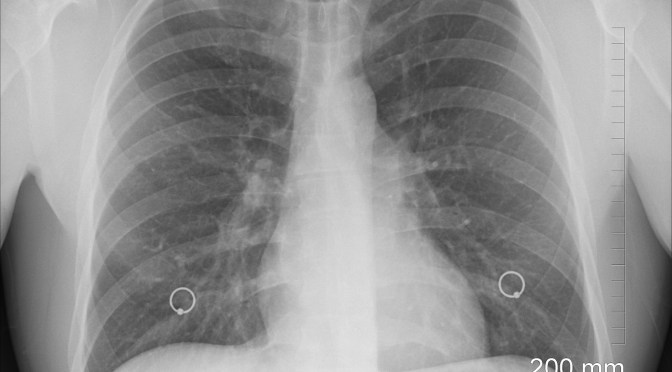

Your lung function is an important predictor of health and longevity

Lung capacity is defined as the maximum amount of air the lungs can hold, while lung function involves the speed with which you can inhale and exhale. Lung function also involves how efficiently your lungs oxygenate the blood, while at the same time removing carbon dioxide.